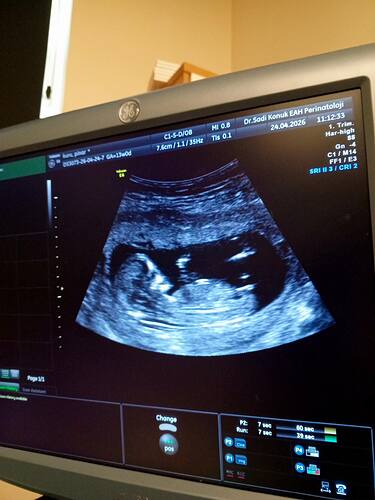

yeni fotografla geldim cinsiyet tahmini alabilirmiyim

Bence kız

Kızz yüksek oranla %80 felan

Kız benceee

Prenses gibi canım bacak arasından bir çıkıntı yok

Kızzz olabiliiir